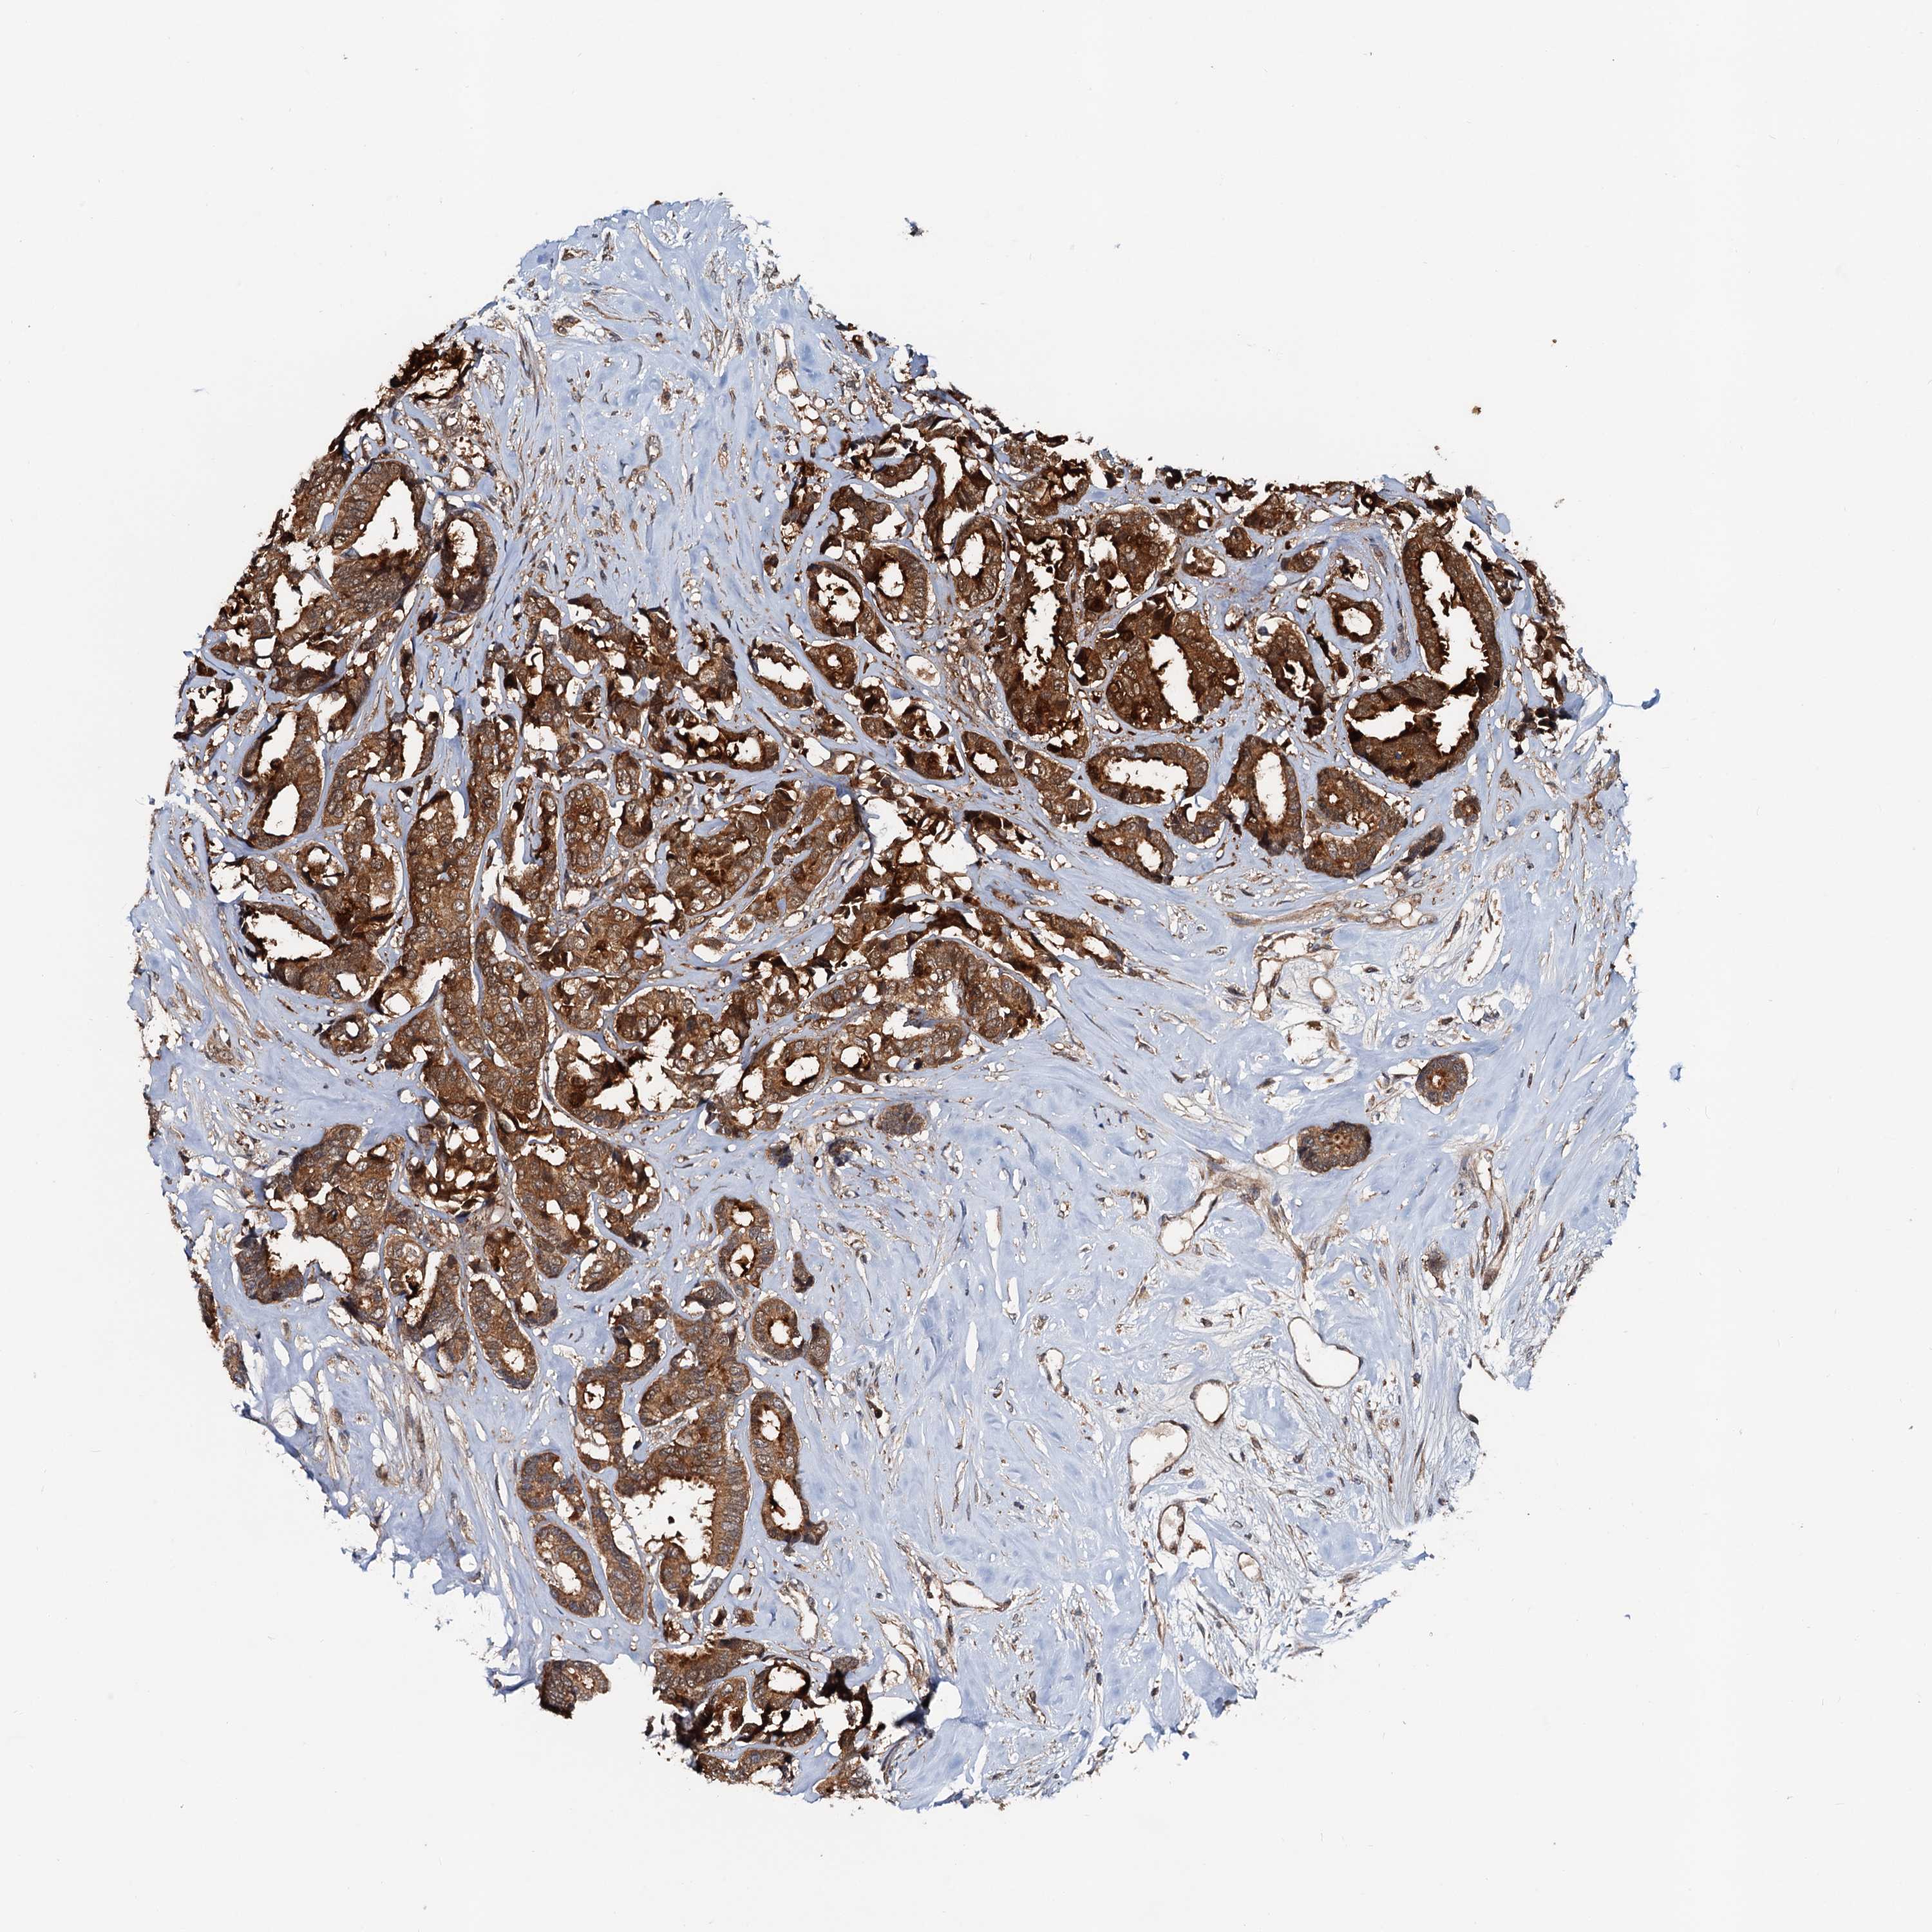

CANCER BREAST CANCER Show tissue menu

BRCA TCGA BRCA VALIDATION PROTEIN EXPRESSION